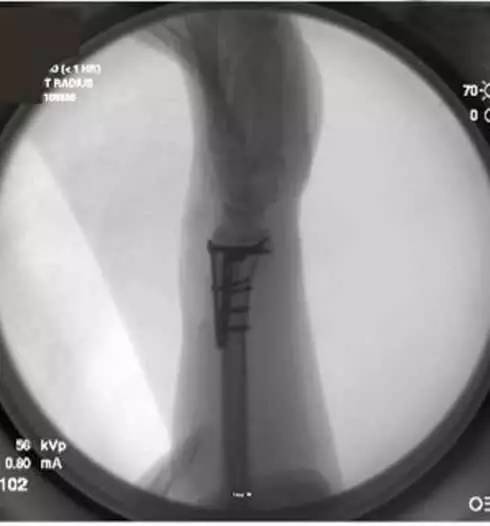

5. 整体复位完成后,放置桡骨远端钢板,以提供稳定和坚强的复位。(图 3)

图 3 放置桡骨远端钢板